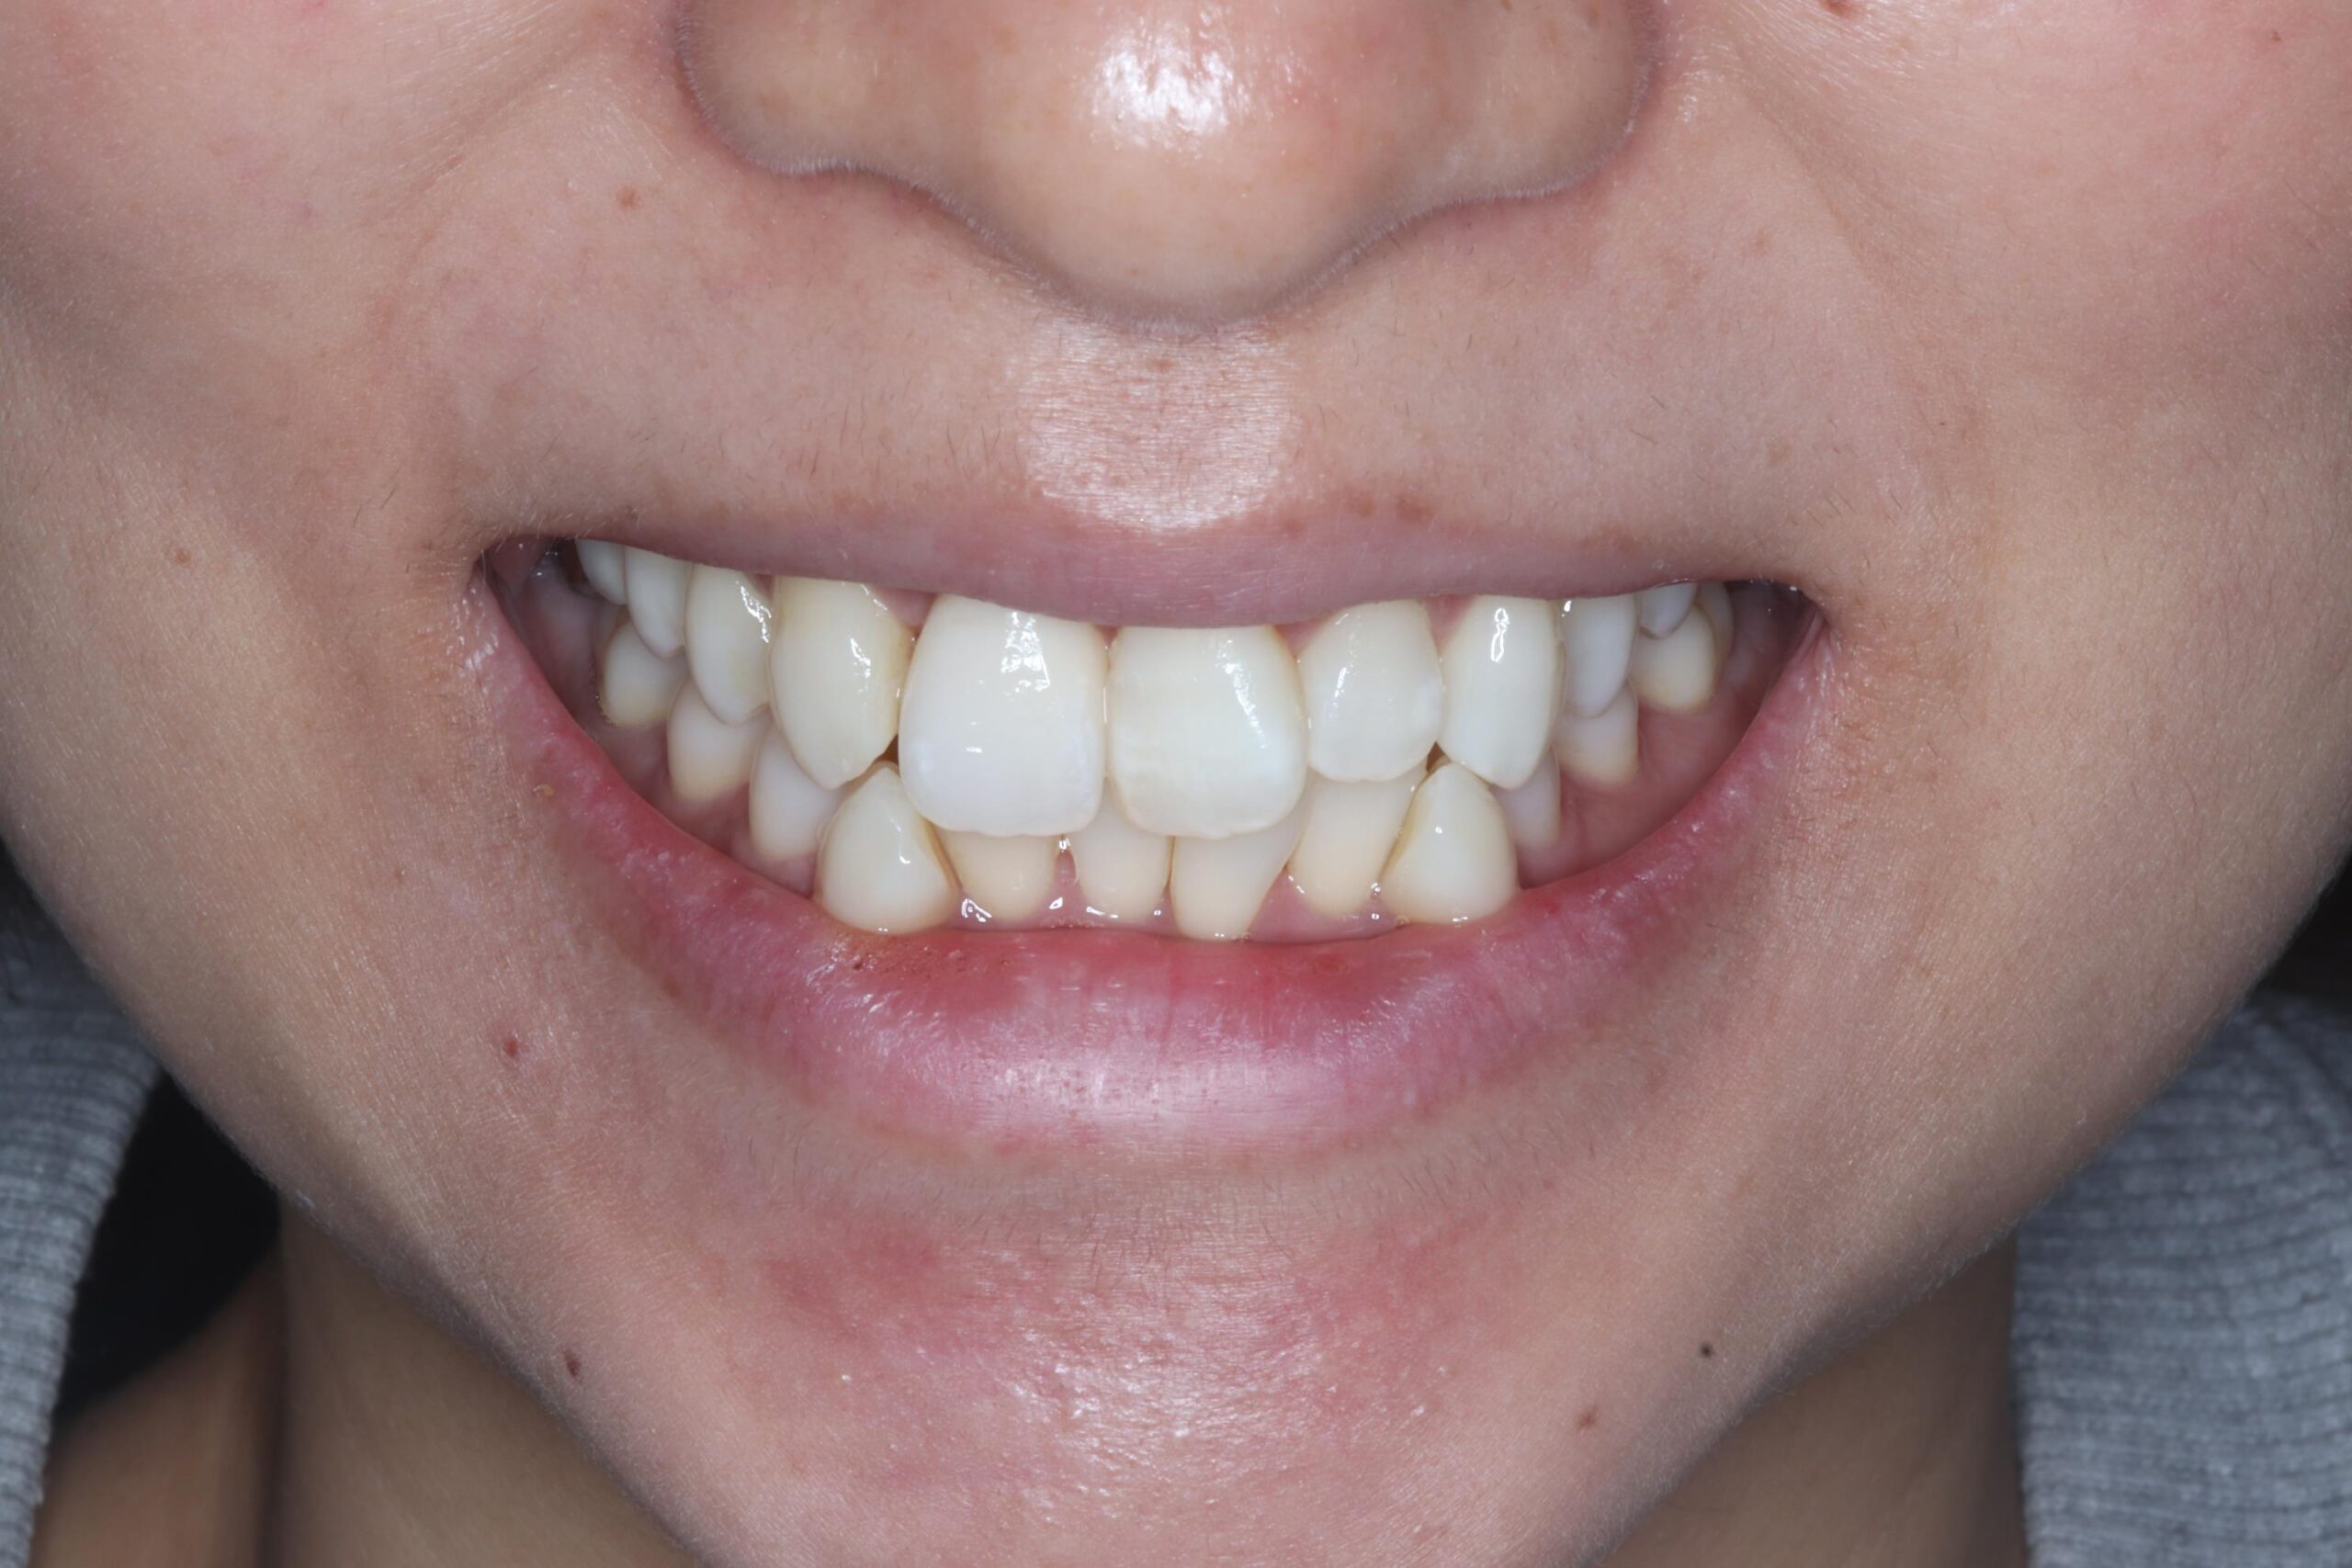

術後正面観

| 主訴 | 前歯の差し歯が折れてしまい、腫れて痛みがある。できるだけ隣の歯を傷つけずに治したい。 |

|---|---|

| 年代・性別 | 30代 男性 |

| 治療部位 | 上顎左側 1 |

| 治療費用 | インプラント手術料 300,000円 |

| 手術回数 | 1回 |

| 治療期間 | 6ヶ月 |

| 手術時間 | 90分 |

| 治療回数 | 4回 |